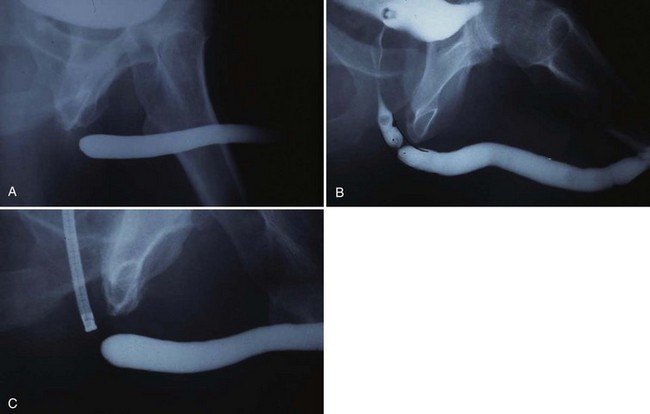

In young patients with severe meatal stenosis, surgery is indicated. Because patients with long-standing meatal stenosis often have severe proximal urethral stricture disease, retrograde urethrography should be performed before the initiation of therapy. The etiology of stricture disease associated with LS is unclear. Possible causes include iatrogenic stricture resulting from repeated instrumentation and pressure voiding associated with meatal stenosis causing secondary intravasation of urine into the glans Littre (Fig. 36–14). In cases of early LS with only meatal involvement resulting in stenosis of the fossa navicularis, prompt reconstruction seems to be successful in the long term and seems to avoid the sequelae of panurethral stricture disease. Most surgeons now believe that because LS is a disease of genital skin, better tissue for reconstruction is the oral mucosa, and techniques are discussed later (Mundy, 1994; Bracka, 1999). Long-standing cases with a long length of urethral stricture are amenable to techniques of reconstruction but are very challenging. It is becoming clear that except in the case of urethral stricture disease confined only to the meatus and fossa navicularis, staged oral graft reconstruction, at least in the short to mid term, seems to provide superior durable results. This may also be the case in cases confined to the meatus and fossa navicularis, because a recent analysis of patients reconstructed with the ventral transverse skin island technique showed a 50% recurrence rate even in those patients. The weakness of that analysis, is that the data did not include biopsy proof that all patients had LS (Virasoro et al, 2007). We also are seeing more and more patients who present with a buried penis. This phenomenon occurs when the skin of the penile shaft has been lost because of severe inflammation, and the penis is trapped in the penopubic and scrotal area. These patients are often profoundly overweight, and many are diabetic; they have often had prior surgical procedures. Their management is complex and ultimately determined by their desire and need for functional reconstruction. In some patients with severe urethral stricture disease, we have completely reconstructed the urethra; in others, we have simply performed a perineal urethrostomy. Perineal urethrostomy is usually technically straightforward, because the rule in most patients with lichen sclerosus is to spare the proximal anterior urethra. We have proposed that, in many cases, the sparing of the proximal anterior urethra demonstrates the distribution of the glands of Littre for a given patient. Younger patients have requested mobilization and release of the penis with placement of a split-thickness skin graft. However, because the inflammation involves the glans penis (which is not removed), the secondary inflammation may also involve the skin graft. Therefore lifelong monitoring of these patients for the secondary effects of inflammation is necessary.

Figure 36–14 A and B, Urethrogram in a patient with urethral stricture disease associated with lichen sclerosus–balanitis xerotica obliterans. It illustrates the intravasation of contrast material into the dilated glands of Littre during voiding.

(From Jordan GH. Management of membranous urethral strictures via the perineal approach. In: McAninch J, Carroll P, Jordan GH, editors. Traumatic and reconstructive urology. Philadelphia: WB Saunders; 1996.)